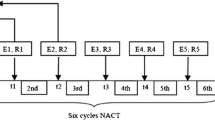

The 2D SWE scanning was performed by one of our two experienced sonographers, using the GE LOGIQ-E9 ultrasound clinical scanner equipped with a 2–8 MHz linear array probe (9L-D, GE Healthcare, Wauwatosa, WI) for both the conventional B-mode and SWE data acquisition. To reduce motion artifacts, patients were instructed to suspend respiration for approximately 3 s during the data acquisition. The SWE measurement was acquired within a rectangle-shaped field of view, which covered the whole lesion and the adjacent normal tissue. For each lesion, along the same orientation, at least four SWE images were obtained. One of the consistent stiffness maps was chosen to draw ROIs. Three non-overlapping ROIs, 3 mm in diameter, were placed at the stiffest position of the lesion, with peritumoral stroma included. One ROI was placed at the surrounding normal tissue. The mean SWS, maximum SWS, minimum SWS, and standard deviation of the SWS inside each ROI were calculated by the ultrasound machine. The SWS for the tumor was represented by the average values of the three ROIs placed at the stiffest position. A new shear wave parameter, mass characteristic frequency, represented by fmass, is used in this paper: fmass = 1000Vmin/d, where fmass is with unit Hz, Vmin is the minimum SWS with unit m/s, and d is the mass size in mm and recorded as the maximum dimension of the tumor shown on the B-mode image. Figure 2 illustrates the measurements for calculating fmass.

An example for calculating the fmass for a 59-year-old female patient with grade II invasive ductal carcinoma. a The mass size d was read as the greatest dimension shown in the clinical B-mode image, and it is 28 mm in this example. b The minimum shear wave speed was calculated as the average value of the minimum shear wave speed from the three ROIs shown in the SWE image and is 2.7 m/s. Therefore, the fmass for this measurement is 96 Hz. ROI, region of interest; SWE, shear wave elastography